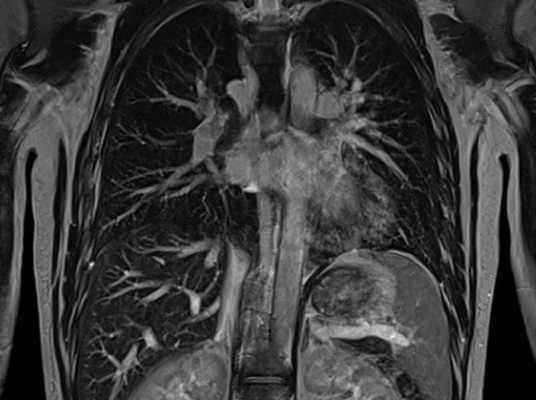

КТ с контрастированием (мягкотканное окно), первое из шести аксиальных изображений: нормальные структуры грудной стенки. На первом срезе визуализируются мышцы грудной стенки в надключичной области. КТ с контрастированием, аксиальный срез через верхушки легких: визуализированные структуры включают нормальные подключичные и подмышечные сосуды. КТ с контрастированием, аксиальный срез через медиальные отделы ключиц: мышцы, прикрепляющиеся к лопатке. КТ с контрастированием, аксиальный срез на уровне ветвей дуги аорты. КТ с контрастированием, аксиальный срез на уровне дуги. КТ с контрастированием, аксиальный срез через субкаринальную область. На первом из шести аксиальных Т1-взвешенных МР-томограмм представлены нормальные структуры грудной стенки. Первый срез выполнен через надключичную область. МРТ, аксиальное Т1-ВИ через верхушки легких. МРТ, аксиальное Т1-ВИ на уровне дуги аорты. МРТ, аксиальное Т1-ВИ на уровне аортолегочного окна. МРТ, аксиальное Т1-ВИ через легочные артерии. МРТ, аксиальное Т1-ВИ через нижние доли легких и нижние легочные вены. КТ с контрастированием (костное окно), первое из шести корональных изображений спереди назад: мышцы грудной стенки в норме. Первый срез получен на уровне грудино-ключичных суставов. КТ с контрастированием, корональный срез на уровне легочных артерий. КТ с контрастированием, корональный срез на уровне киля трахеи. КТ с контрастированием, корональный срез на уровне нисходящего отдела грудной аорты. КТ с контрастированием, корональный срез на уровне грудного отдела позвоночного канала. КТ с контрастированием, корональный срез на уровне задних отрезков ребер и остистых отростков. Первая из шести корональных Т1-взвешенных МР-томограмм: нормальные структуры грудной стенки (спереди назад). Первый срез получен через медиальные отделы ключиц. МРТ, корональное Т1-ВИ на уровне подключичной вены. МРТ, корональное Т1-ВИ на уровне подключичных артерий и переднего отдела плечевого сплетения. МРТ, аксиальное Т1-ВИ через плечевое сплетение и превертебральные структуры. МРТ, аксиальное Т1-ВИ через грудной отдел позвоночного канала. МРТ, аксиальное Т1-ВИ через задние отрезки ребер. Рентгенограмма, фокусированный вид, заднепередняя проекция: частично визуализируемая рукоятка грудины, грудино-ключичные суставы, характерный ход первых ребер и их сочленения с латеральными краями рукоятки грудины. КТ с контрастированием (костное окно), сагиттальный срез: у мужчины 25 лет определяется нормальная анатомия грудины, визуализированы рукоятка, тело и мечевидный отросток.